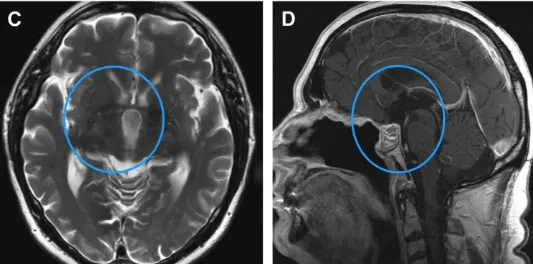

施罗德教授在内镜下行全切术,包括已被肿瘤浸润破坏的部分垂体柄。术后2年MRI未见肿瘤复发(C, D)。水肿完全消退(C)。图像(D)也显示鼻中隔皮瓣重建颅底。

术后该患者经历了短暂的神志不清,但神志及认知功能恢复迅速,且体重保持稳定。垂体柄部分切除后,需要进行激素替代治疗。术后两年随访,颅咽管瘤未见复发,水肿完全消退。